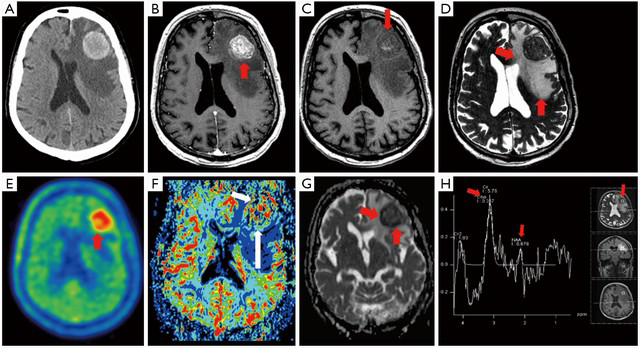

There are two main types of Neuroimaging techniques and they are Structural and Functional. Structural Neuroimaging includes CT scans and MRI's and Functional Neuroimaging includes PET scans and fMRI's.

• Structural and Functional Neuroimaging

Structural and Functional Neuroimaging

Structural:

CT scans- Computerised Temography, takes x-rays of the brain at different angles, able to locate tumors and strokes.

MRI- Magnetic Reasoning Imaging, able to show very fine tissue in detail, diagnoses structural abnormalities. Functional:

PET- Position Emission Tomography, shows brain function, measures brain activity.

fMRI- Functional MRI, measures brain activity, records levels of activity in different parts of the brain.